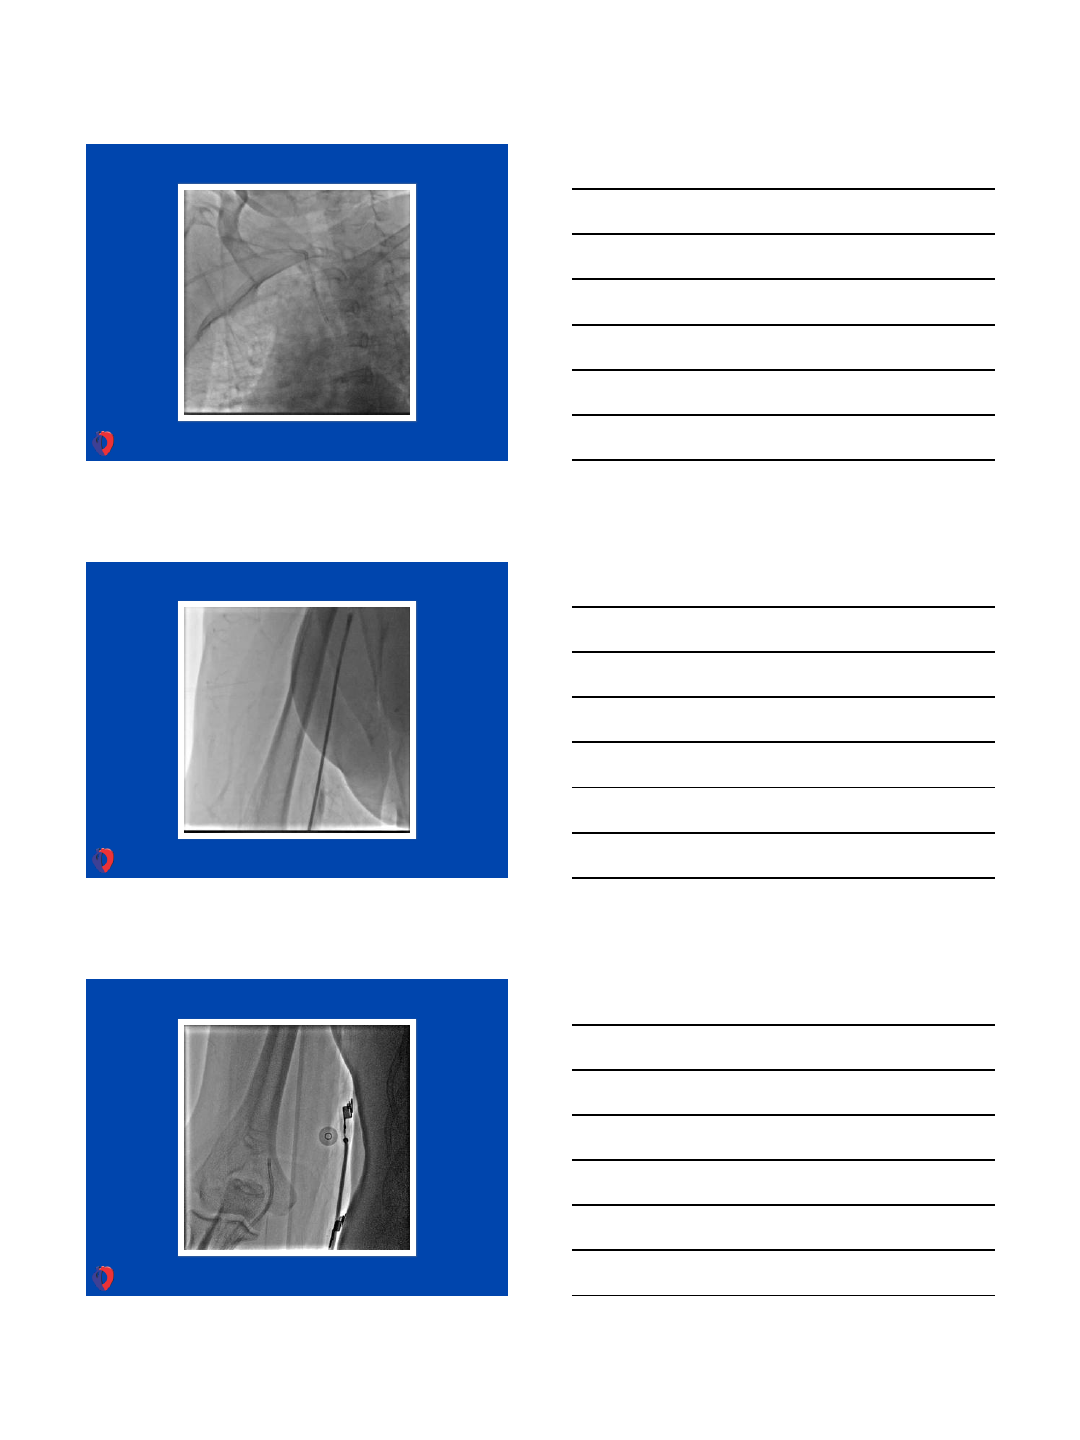

Next step - tight subclavian stenosis - to treat or not to treat

…..???

Stent 6,0/14mm (18 atm = 6,99mm) without

guiding catheter …

Final result of pPCI and subclavian stenting

31.5.2013